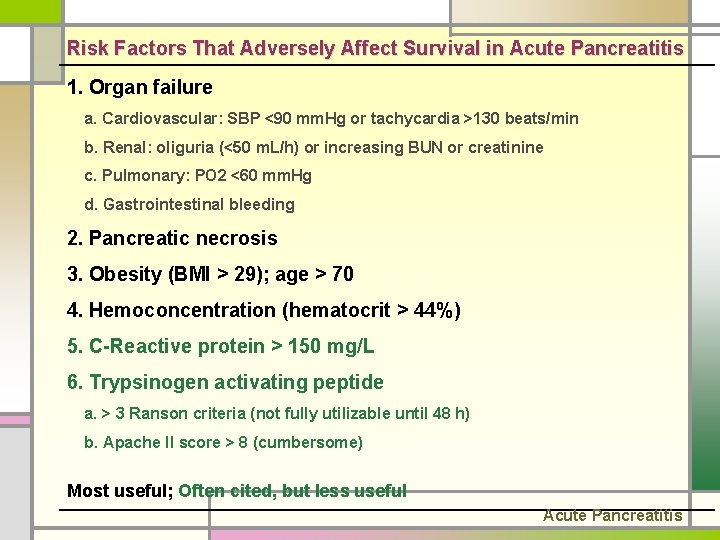

Risk Factors That Adversely Affect Survival in Acute Pancreatitis 1. Organ failure a. Cardiovascular: SBP <90 mm. Hg or tachycardia >130 beats/min b. Renal: oliguria (<50 m. L/h) or increasing BUN or creatinine c. Pulmonary: PO 2 <60 mm. Hg d. Gastrointestinal bleeding 2. Pancreatic necrosis 3. Obesity (BMI > 29); age > 70 4. Hemoconcentration (hematocrit > 44%) 5. C-Reactive protein > 150 mg/L 6. Trypsinogen activating peptide a. > 3 Ranson criteria (not fully utilizable until 48 h) b. Apache II score > 8 (cumbersome) Most useful; Often cited, but less useful Acute Pancreatitis